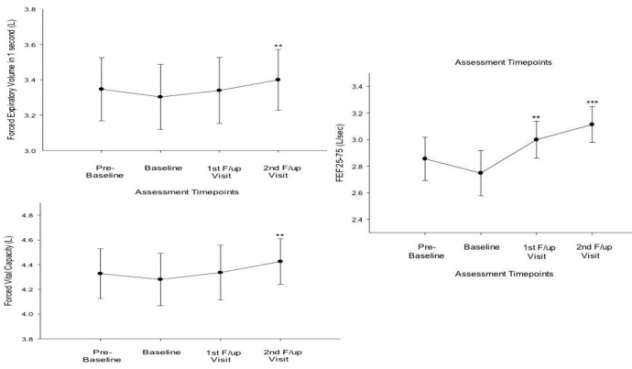

При проведении клинических испытаний было выяснено, что, несмотря на пар, электронные сигареты не имеют существенного влияния на астматиков. 18 пациентов-астматиков заменили курение вейпингом. Спустя шесть месяцев и год провели повторные замеры объема легких. Результаты вы можете видеть на графиках ниже: